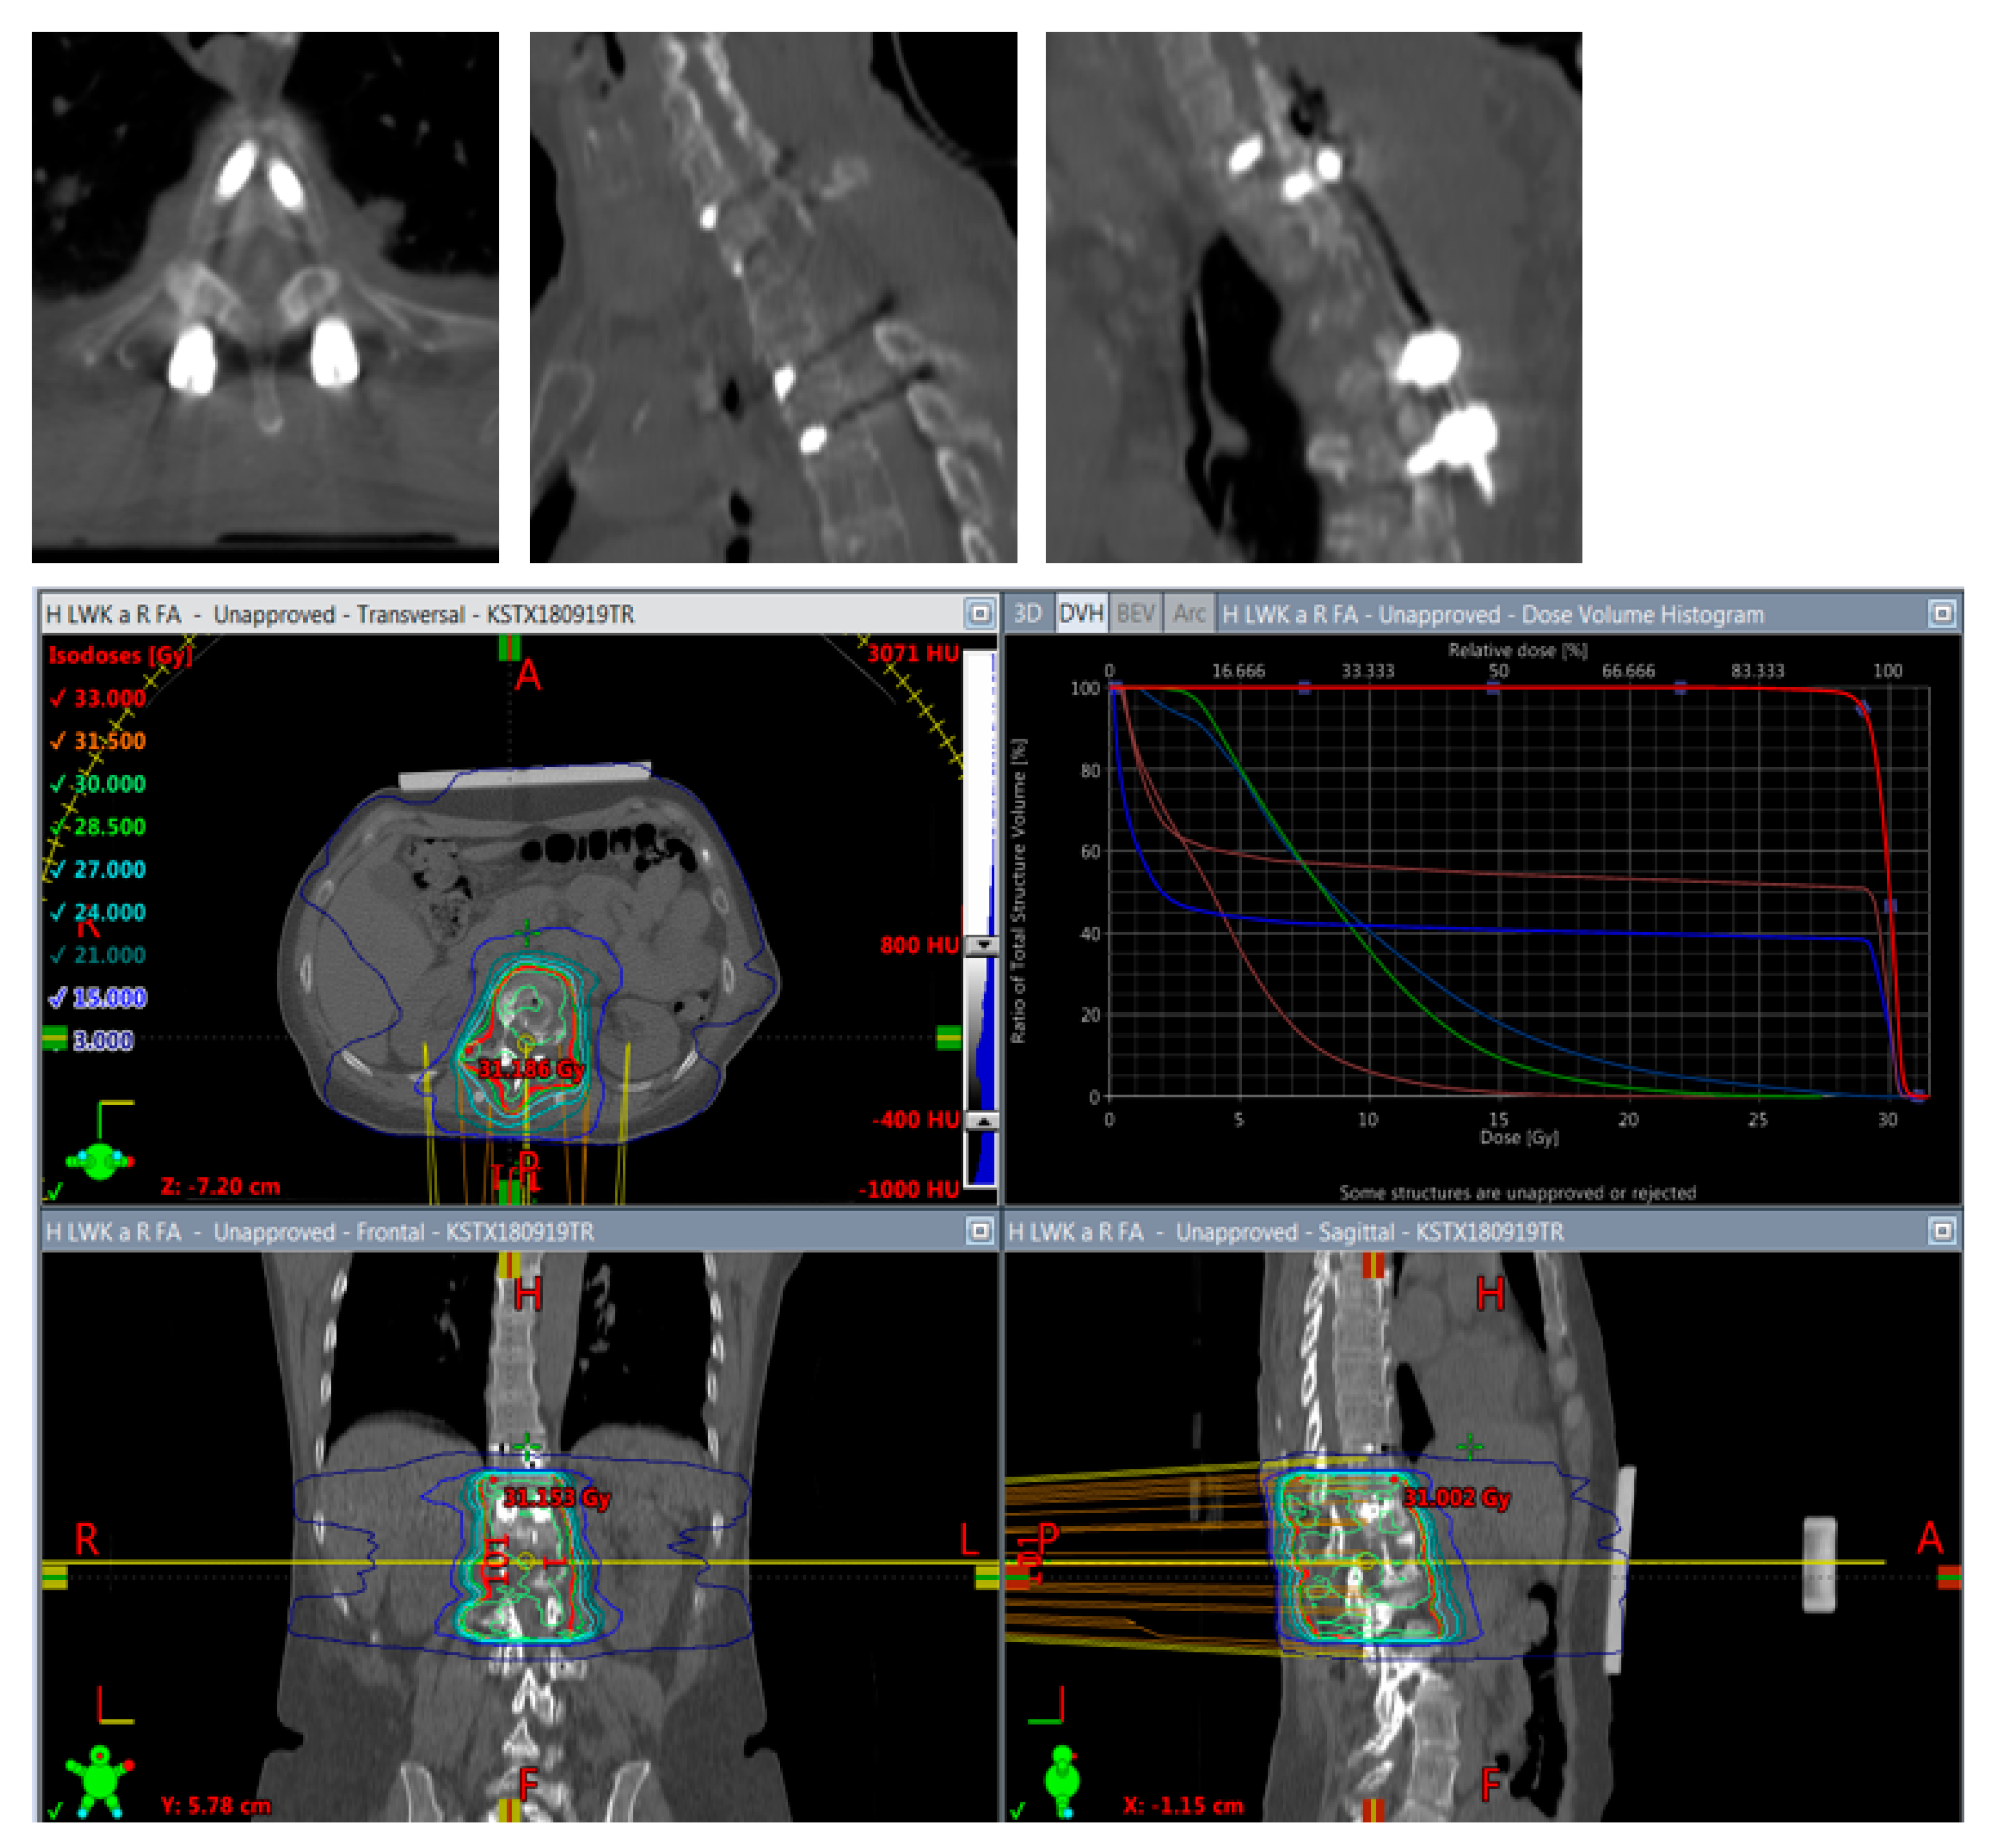

So far, pedicle screws and rods made of titanium or cobalt–chrome alloys were used for spinal instrumentation. However, these highly absorbing materials lead to artifacts in computed tomography (CT) scans, hampering CT image-based radiotherapy planning [12]. Recently, carbon-fiber-reinforced (CFR) polyethyl-ether-ether-ketone (PEEK) pedicle screw systems were introduced. CFR-PEEK reduces artifacts on CT and magnetic resonance imaging (MRI) and shows less perturbation effects on photon radiation than titanium [13,14,15]; thus, radiotherapy can be planned and applied more precisely and follow-up images can be analyzed better with respect to tumor recurrence (Figure 1 and Figure 2). A cadaver study has demonstrated the biomechanical non-inferiority of CFR-PEEK pedicle screws compared to titanium [16]. We and other authors have previously reported our clinical experience with CFR-PEEK implant systems as a viable alternative for patients with spinal neoplasms [13,17,18,19,20]. However, a large safety and efficacy study of CFR-PEEK spinal stabilization systems does not exist so far. Therefore, we analyzed a consecutive series of 321 patients undergoing posterior stabilization for SM and primary bone tumors of the spine using CFR-PEEK pedicle screws.

Figure 1.

Exemplary case of tumor recurrence. (A–C): preoperative MRI of thoracic metastasis from urothelial carcinoma (T1 contrast enhanced). (D–G): follow-up MRI after CFR-PEEK instrumentation showing tumor recurrence ((D): T2; (E–G): T1 contrast enhanced).